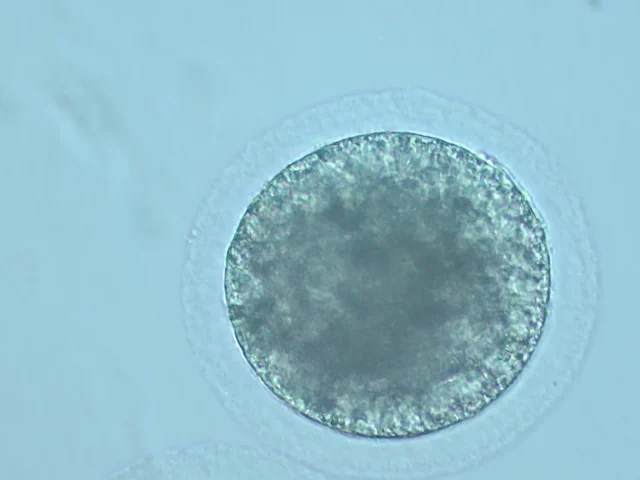

MAXIMIZA EL NÚMERO DE EMBRIONES POR YEGUA AL AÑO

CONSIGUE EMBRIONES DURANTE TODO EL AÑO

CRIOPRESERVACIÓN DE CÉLULAS EN NUESTRO BANCO GENÉTICO

MAXIMIZA EL NÚMERO DE EMBRIONES POR YEGUA AL AÑO

CONSIGUE EMBRIONES DURANTE TODO EL AÑO

CRIOPRESERVACIÓN DE CÉLULAS EN NUESTRO BANCO GENÉTICO

Laboratorios equipados con la última tecnología para salvaguardar el patrimonio genético del caballo.

Banco genético

Amplio banco de células para realizar las diversas técnicas de reproducción asistida.